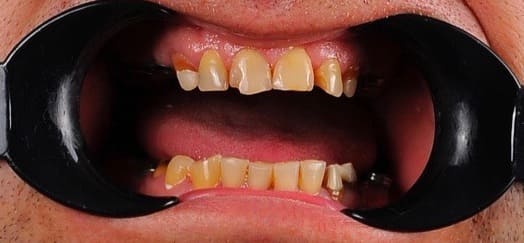

До

Неравномерная патологическая стираемость зубов. Установлены импланты в боковых отделах верху и внизу. Протезирование на имплантах циркониевыми коронками+ виниры на передние зубы.